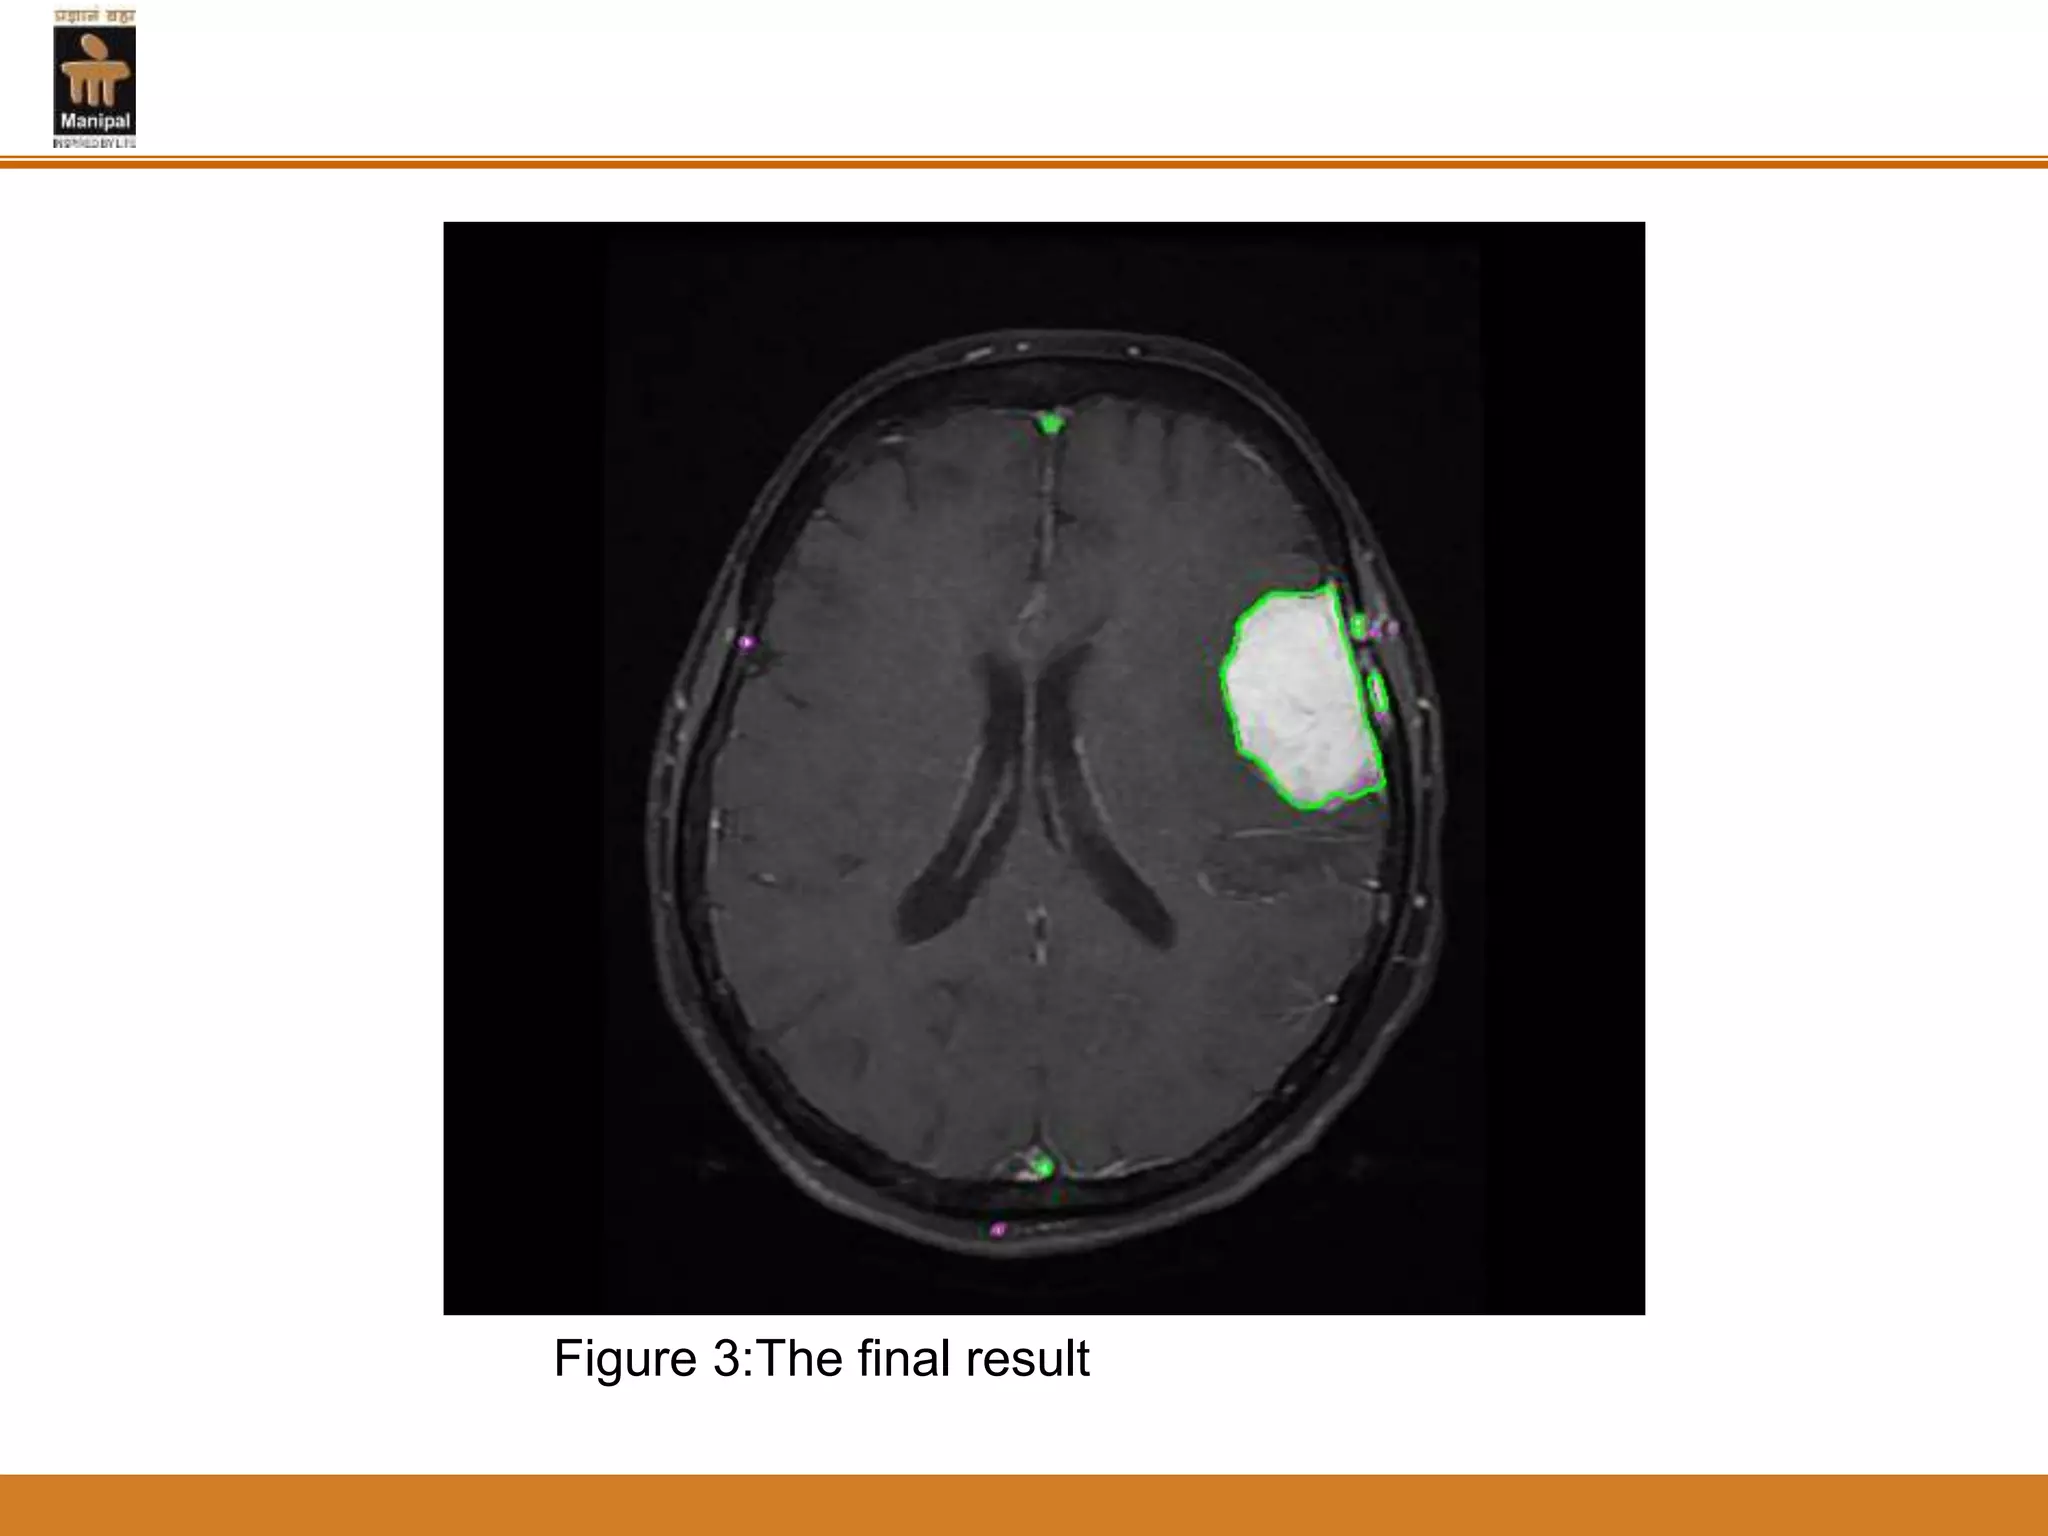

Figure1: Fuzzy C-means clustering (FCM) applied to the MRI

Figure 2: A level set segmentation

Figure 3:The final result